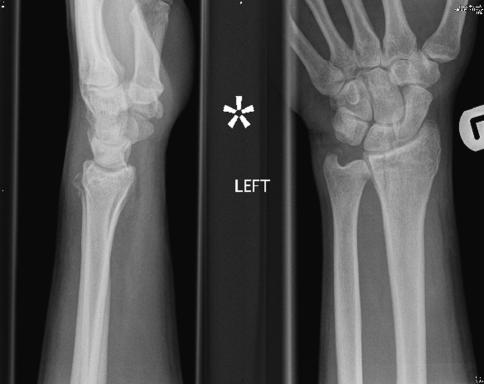

The distal ulna represents the fixed point around which the radius and the hand acts in daily living. The significance of distal ulnar fractures is often not appreciated and often results in inadequate treatment in comparison to its larger counterpart; the radius. There is little guidance in the current literature as how to manage these fractures and their associated injuries. This paper aims to critically review the current literature and combine it with treatment suggestions based on the experience of the authors to help guide investigation and management of these often complex injuries.

尺骨远端是桡骨和手部在日常生活中活动所围绕的固定点。尺骨远端骨折的重要性常常未得到重视,与更为常见的桡骨骨折相比,其治疗往往不够充分。目前的文献中关于如何处理这些骨折及其相关损伤的指导很少。本文旨在批判性地回顾当前文献,并结合作者的经验提出治疗建议,以帮助指导对这些通常较为复杂的损伤的检查和处理。